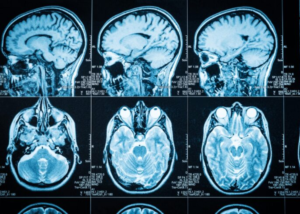

The lack of organization on the roads isn’t just jarring for me. Road injuries and falls are major causes of traumatic brain injury (TBI) and spinal cord injury (SCI), which contribute heavily to the global burden of disease. That burden, as one might expect, is borne disproportionately by low- and middle-income countries.

It might be hard to believe that incidence of TBIs is on the rise, when many are preventable; with the emphasis on structural changes in policy to influence public health in countries like the United States, road injuries should be declining. Researchers in the 2016 Global Burden of Disease group identified increases in population density, an aging population, and the growth of motor vehicle/motorcycle/bike use worldwide, as potential reasons for the growing impact of TBIs and SCIs. The toll this takes isn’t limited to its horrible toll on victims and their families. The economic burden of TBIs can be immense because of the specialized care it requires.